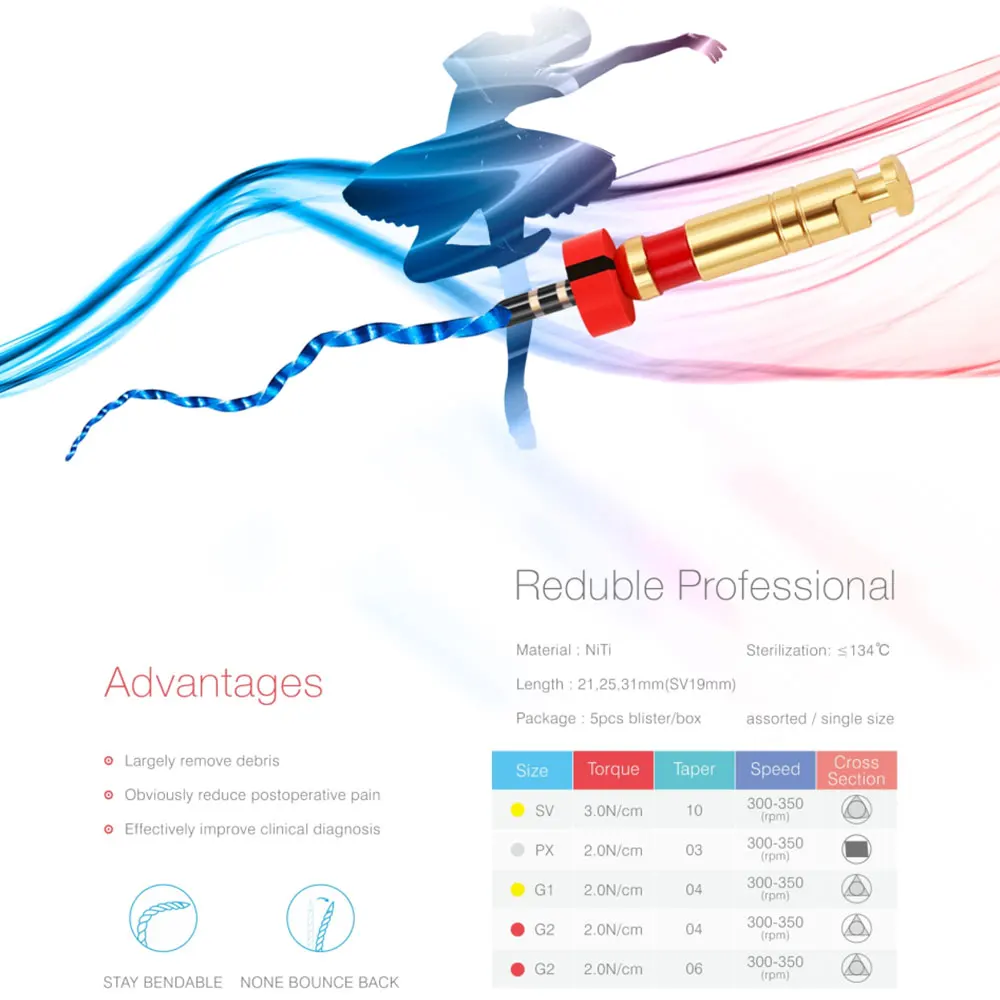

5pcs/pack Dental Rotary Files 25/.04 25/.06 20/.07 15/.03 20/.04 Used For Dental Endodontic NITI Files Rotary Instruments